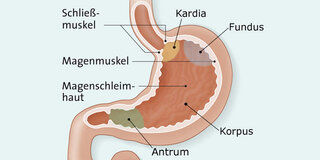

Anatomie: So ist der Magen aufgebaut.

© W&B/Jörg Neisel

Anatomisch gesehen ist der Magen (Fachbegriff: Ventriculus) lediglich ein dehnbarer, elastischer Muskelsack, der an die Speiseröhre anschließt. Er besteht aus Magenmund (Kardia), Magengrund (Fundus), Magenkörper (Corpus) und Magenausgang (Antrum). Er mündet in den Zwölffingerdarm (Duodenum), den ersten Abschnitt des Dünndarms.